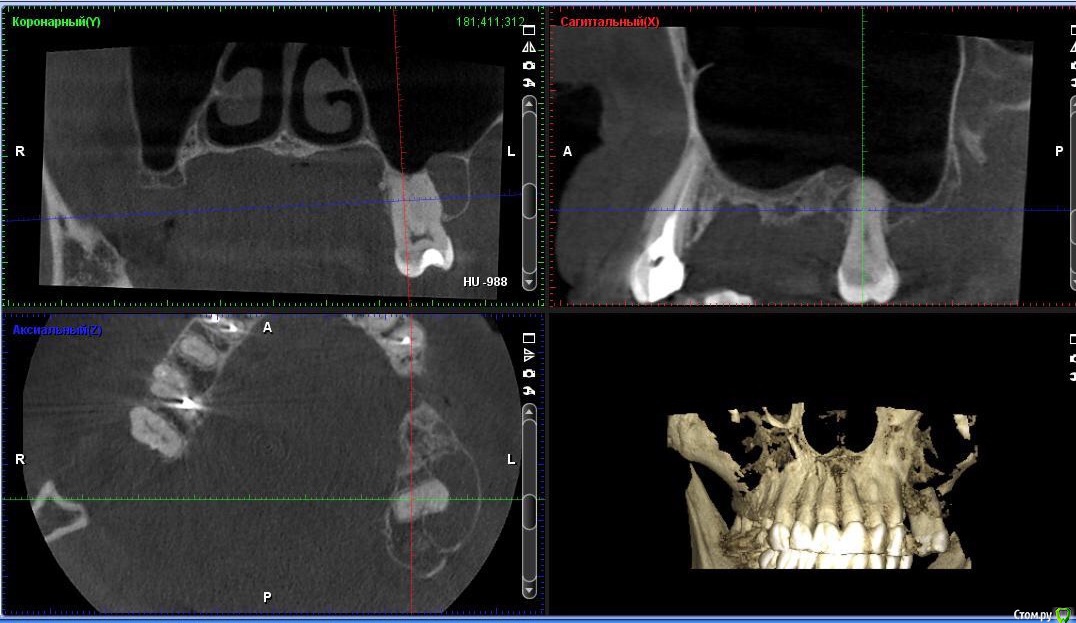

togrul Опубликовано 6 апреля, 2017 Поделиться Опубликовано 6 апреля, 2017 (изменено) Добрый день коллеги . Необходима Ваша помощь в планировании лечения. Пациентке нужно установить 2 имплантата в позиции 24-26. При анализе кт пришёл к выводу : 1 - провести НКР для восстановления высоты сеткой , через 6 месяцев установка имплантатов . 2- в области 27 зуба есть радикулярная киста , как вы считаете ее нужно убирать или нет и радикулярная ли данная киста? 3 - нужно ли проводить синус с нкр или лучше провести после НКР закрытый синус ? Буду благодарен за ответы.IMG_3292.BMPIMG_3293.BMPIMG_3294.BMP Изменено 6 апреля, 2017 пользователем togrul Ссылка на комментарий

Хью Крейн Опубликовано 6 апреля, 2017 Поделиться Опубликовано 6 апреля, 2017 Киста есть. Убирать лучше с зубом. Т.к. эндолечение вряд ли будет эффективно.Вестибулярно у зуба кости очень мало. Между кистой и верхнечелюстным синусом костная стенка есть. Синус лучше открытый,вместе с НКР. И ждать от 6 месяцев.Я бы сделал так. Ссылка на комментарий

togrul Опубликовано 6 апреля, 2017 Автор Поделиться Опубликовано 6 апреля, 2017 Спасибо за комментарий. Просматривая кт зуб 27 не вовлечен в полость кисты. Я завтра скину срезы другии, Но слизистая шнайдеровой мембраны сращена на мой взгляд с кистой . И еще один момент это рубец на границе неподвижной слизистой к подвижной. Ссылка на комментарий

CToMaToJlor Опубликовано 30 августа, 2017 Поделиться Опубликовано 30 августа, 2017 а полостное образование к 7 точно имело отношение? а то по представленным срезам мне это не показалось очевидым 1 Ссылка на комментарий

togrul Опубликовано 31 августа, 2017 Автор Поделиться Опубликовано 31 августа, 2017 (изменено) а полостное образование к 7 точно имело отношение? а то по представленным срезам мне это не показалось очевидымНет не имело. но проведя холодовой тест, зуб не реагировал. было принято решение его депульпировать. И вовремя лечения терапевт отметил, что пульпа практически была некротизирована. Изменено 31 августа, 2017 пользователем togrul Ссылка на комментарий